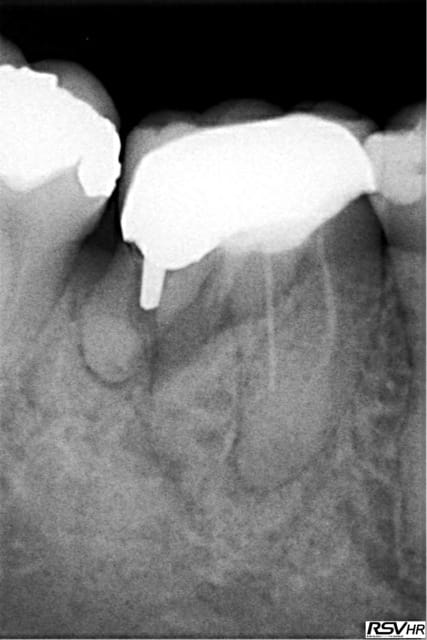

Alors voilà le premier cas :

EII sur 24 du 16/09/10

Obtention d'une stabilité primaire, mais plutôt fragile.

Temporisation par bridge Maryland collé sur une couronne métal en distal, ce qui a été la cause de multiple descellements, et possible traumatismes de l'implant via sa vis de cicat.

Manifestement une autre cause possible est la présence d'une infection maousse en dans le site le jour de la pose...

Qui dit la faute à Tekka ?